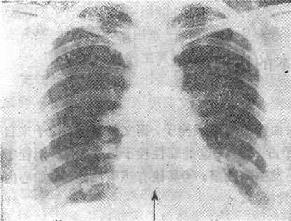

图116-1 肺梗死